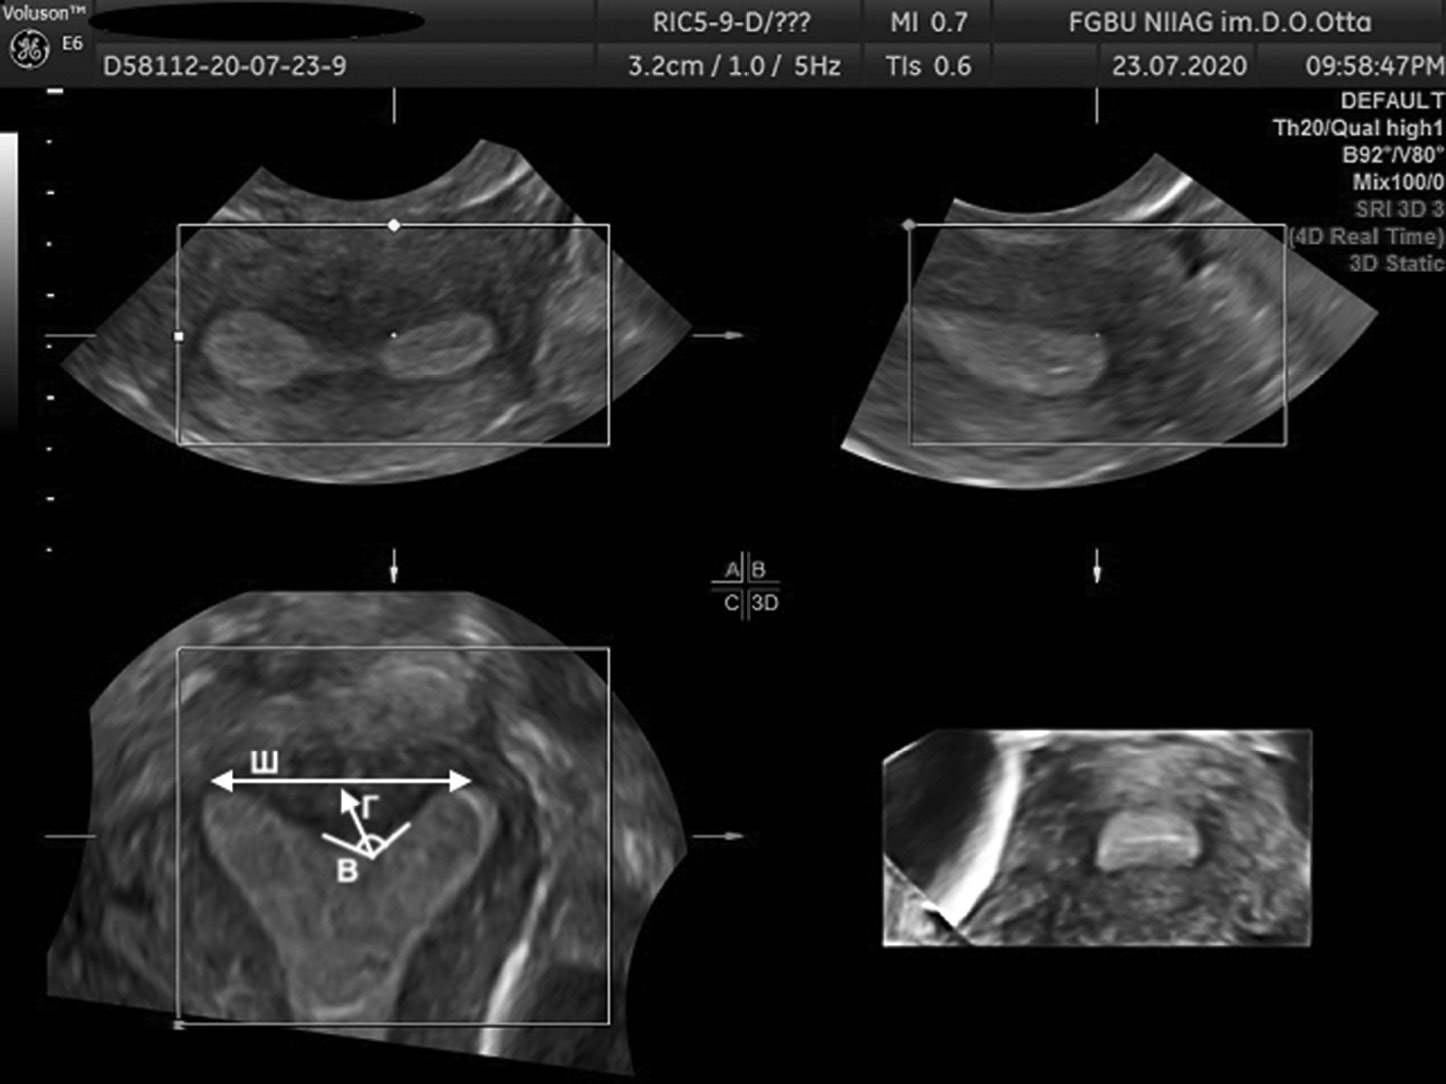

The AFS proposed to assess parameters, such as Г, cavity indentation; Ш, uterine cavity width; and B, angle of cavity indentation (Figs. 1–4).

Fig. 2. 3D ultrasound reconstruction of the uterine cavity: arcuate uterus, where Ш, uterine cavity width; Г, cavity indentation; B, angle of cavity indentation (120°)

Рис. 2. Ультразвуковая 3D-реконструкция полости матки — седловидная матка: Ш — ширина полости матки; Г — глубина вдавления полости матки; угол В — угол вдавления полости (120°)

Uterine septum is diagnosed using the following indicators: Г ≥15 mm, angle B <90º, while uterus arcuate is diagnosed using the following indicators: D ≥10 mm, but <15 mm and angle B >90° [11].